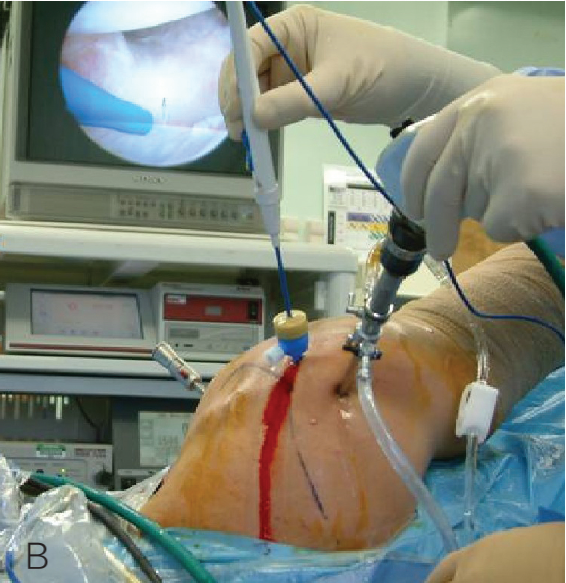

街舞兴起,篮球、羽毛球、网球运动场地也越来越多,这些年越来越多的投掷肩患者,手术也能够在关节镜下微创开展了。本文整理了投掷肩手术的前后操作及注意事项,供大家参考。

术前准备体位

P,后方入路:首先建立,是主要的探查入路。 A,直接前方入路:主要的操作入路;多用途的;可用于诊断性关节镜检查,肩袖关节内面的清理及后方探查。 LA,低位前方入路:位于肩胛下肌腱上缘的正上方;该操作入路用于置入锚钉、关节囊紧缩,前方盂唇修复或关节囊缝合术的打结。 AS,前上方入路:位于肱二头肌滑车前方肩袖间隙的高位;用于从 11 点钟到 1 点钟位置上盂唇修复锚钉的置入;SLAP 修补打结;前方盂唇修复时理想的探查视野,或用于后方盂唇和关节囊的探查。 L,外侧入路:用于进入肩峰下间隙,肩袖修复。 7,后外侧入路(7 点钟位置):B 辅助入路用于后方盂唇锚钉的置入和修复。

上盂唇修复

创建前方和后方入路时,与关节盂面成恰当角度,以便锚钉的置入。 高位和外侧放置前方入路可以有效地进行单纯上盂唇的修复。该入路位于肩袖间隙的高位和外侧,用腰椎穿刺针进行定位。非刚性套管有助于在肱二头肌腱附着部后方置入锚钉。 可用于 SLAP 修复的辅助入路包括 Wilmington 入路(肩峰后外侧角前方、外侧各 1 cm 处)或 Neviaser 入路(锁骨、肩峰、肩胛冈组成的三角形内,肩峰内侧 1 cm 处)。

B. 应首先用腰椎穿刺针确定辅助入路的恰当位置和方向。然后在皮肤上做一个小切 A B 口,钻头导向器置入关节。